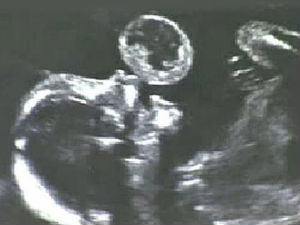

மியாமி: 17 வார கருவின் வாயில் இருந்த புற்றுநோய்க் கட்டி அகற்றம்

மியாமியைச் சேர்ந்தவர் டாம்மி கோன்சாலஸ். அவர் கர்ப்பமாக இருந்தபோது மயாமியில் உள்ள ஜாக்சன் மெமோரியல் மருத்துவமனைக்கு பரிசோதனைக்கு சென்றார். அப்போது 17 வார கருவை ஸ்கேன் செய்த டாக்டர்கள் அதன் வாயில் டென்னிஸ் பந்து அளவுக்கு புற்றுநோய்க் கட்டி இருப்பதைப் பார்த்து அதிர்ச்சி அடைந்தனர். உடனே கருவைக் கலைக்க வேண்டும், அல்லது வயிற்றில் இருக்கும் கருவுக்கு ஆபரேஷன் செய்ய வேண்டும் என்று டாக்டர்கள் தெரிவித்தனர்.

கருவைக் கலைக்க மனமில்லாத டாம்மி ஆபரேஷனுக்கு சம்மதித்தார். இதையடுத்து லேசர் சிகிச்சை மூலம் கருவின் வாயில் இருந்த புற்றுநோய்க் கட்டி அகற்றப்பட்டது. அதன் பிறகு 5 மாதம் கழித்து அழகிய பெண் குழந்தை லேனா வாயில் வடுவுடன் பிறந்தது. தற்போது 20 மாத குழந்தையாக இருக்கும் லேனாவின் வாயில் அந்த வடு தெரியவில்லை.

மேலும் தனது மகள் ஆரோக்கியமாக இருப்பதாக டாம்மி தெரிவித்துள்ளார். 2010ம் ஆண்டு மே மாதம் ஜாக்சன் மெமோரியல் மருத்துவமனையில் இந்த ஆபரேஷன் நடந்தது என்பது குறிப்பிடத்தக்கது.

கருவில் உள்ள குழந்தைக்கு ஆபரேஷன் செய்து புற்றுநோய்க் கட்டி அகற்றி இருப்பது இதுவே முதல் முறையாகும்.